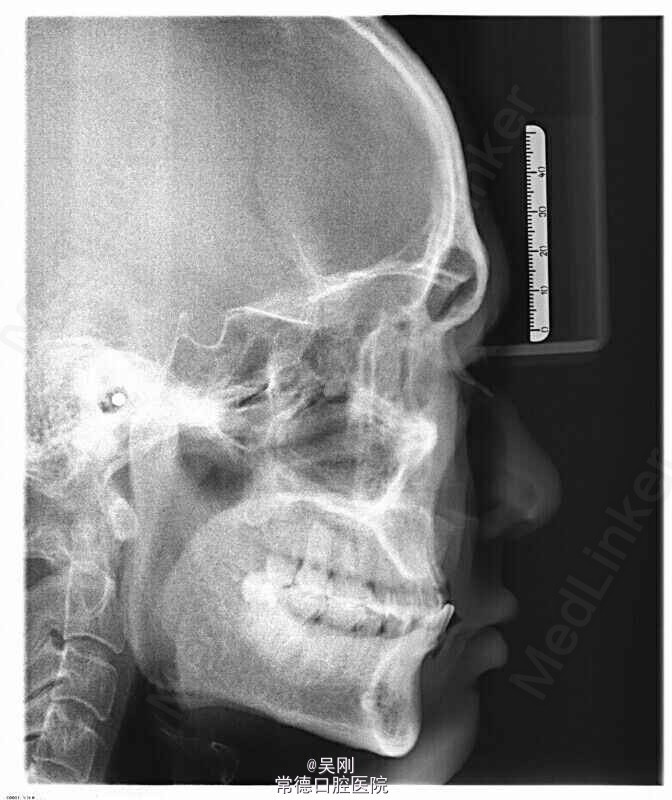

上颌牙列缺损。 1.戴 牙合 垫,暂时恢复美观并为粘固下颌托槽开辟间隙。为防止 牙合 垫压低后牙而影响定位咬合关系,牙合 垫在前磨牙处不接触,距离抬高到能粘固托槽就好,尽量缩短佩戴时间。 2.将托槽按同一平面粘固,前牙减径约1mm(加上本身的间隙共产生约2.5mm),直接用圆丝(硬丝)挂一类牵引,使前牙牙轴具有舌向关闭间隙。 3.基牙预备,因缺牙区跨度超过实际长度选择增加14做基牙。 4.完成烤瓷桥。 5.X线显示磨牙还是有点牙低,下前牙明显内收,于上颌牙槽嵴关系改善。 6.因磨牙压低,下前牙舌侧固定保持。磨牙自己建 牙合 。

分别一个月,三个月,两年共复查三次。磨牙咬合建立,烤瓷桥无异常。 1.完成后才想到其实可以用保持器的膜片加自凝树脂做上颌全牙列合垫,可以避免磨牙压低。 2.下前牙用硬的圆丝关间隙,最大幅度的使下切牙舌倾。 3.因牙槽骨吸收较多,看上去牙弓弧度不大似乎不需要增加基牙,但烤瓷桥要做到美观上唇侧比较饱满略微唇倾,戴上后变相的增加前牙弧形突度,因而增加基牙对抗。 望各位老师提供更好的建议,以便以后遇到可以更完善。